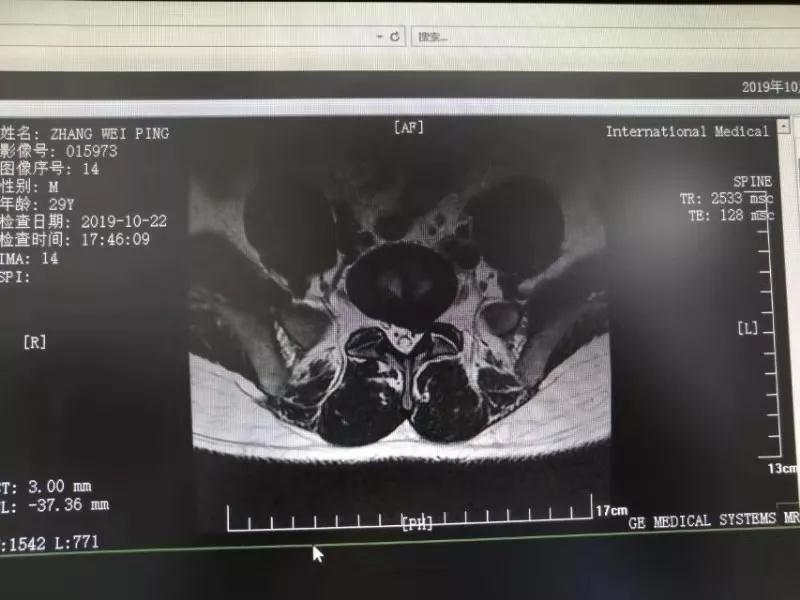

10月25日,29歲的患者小張了解到西安國際醫(yī)學(xué)中心骨科醫(yī)院專家云集,一大早便在家人的陪同下,來到西安國際醫(yī)學(xué)中心骨科醫(yī)院就診。“我腰痛持續(xù)2年多,最近感冒后腰痛癥狀明顯加重了?!毙埫媛犊喑?yàn)殚L期腰痛、左下肢放射性疼痛,她晚上睡覺不能平躺,經(jīng)常疼得睡不著,需要口服止痛藥物才能有所緩解。走路走不了多遠(yuǎn)就開始腿抽的疼,嚴(yán)重影響到工作和生活。

結(jié)合患者的檢查以及年齡情況,王自立副院長推薦讓專門研究椎間孔鏡技術(shù)王雄勛主任給小張做微創(chuàng)的椎間孔鏡手術(shù)。該手術(shù)創(chuàng)傷很小,不影響脊柱的穩(wěn)定性,尤其適合于椎間盤突出的年輕患者,懷著對(duì)骨科醫(yī)院專家的信任,小張與家人商議后,接受手術(shù)治療。